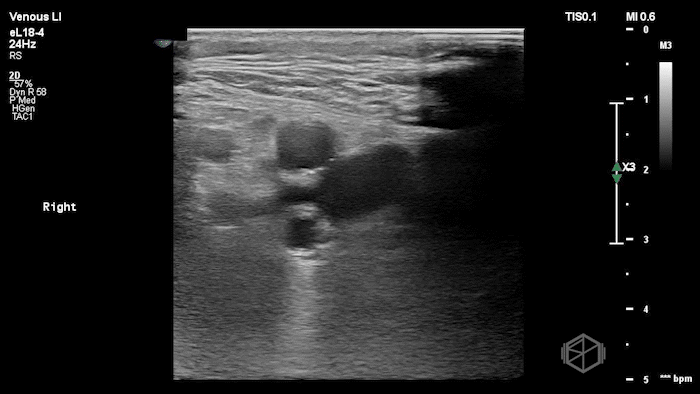

A lower extremity DVT ultrasound performed by Dr. Koutsounadis demonstrated the following:

The POCUS shows a right common femoral vein thrombus. Family members reported that the patient had previously been diagnosed with a DVT very recently and was on apixaban.

The thrombus appeared predominantly hypoechoic to nearly anechoic, making it difficult to appreciate on B-mode imaging alone. However, incomplete compressibility of the vein confirmed the presence of thrombus.

Diagnosis: Right common femoral partially occlusive DVT